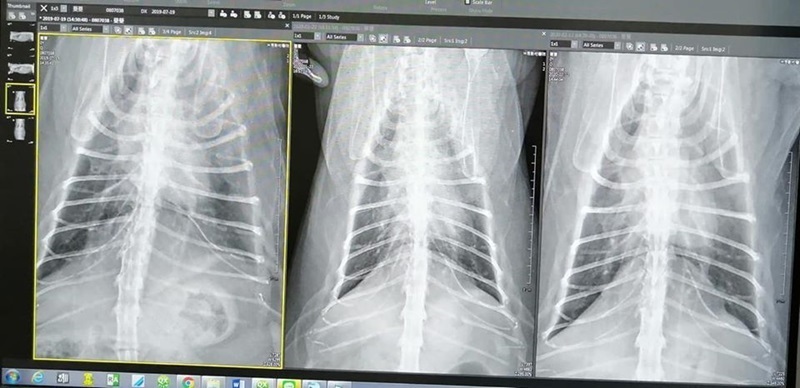

X光檢查發現肺部異常,出現有慢性胸膜炎,也就是肺的外部發炎,看來已有段時間了,可能原因有自體免疫性問題、環境空氣、肺部分泌物等,先以氣霧二週治療。

原本擔心是有慢性胸膜炎,但蔓蔓並沒有咳嗽情形,X光檢查,肺部及消化系統看來無異常影像,三次日期的X光影像對照無太大變化。

血檢結果,紅白血球正常,腎指數3.5-->3.4 ,BUN正常,今天檢查結果並無發現特別問題,就先再觀察,要特別留意體重變化。